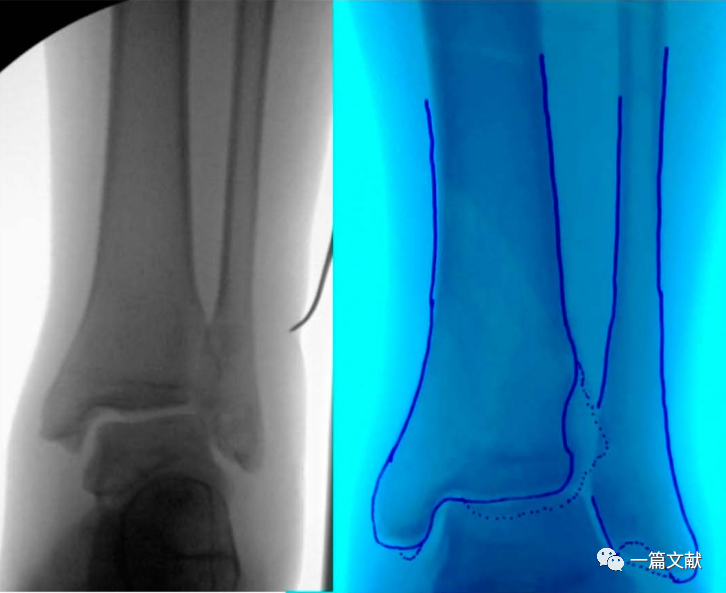

1、踝关节手术

在患者入手术室后,行无菌铺单前对健侧肢体C臂机透视,并将图像保存于右侧显示屏。若术中需要在垫高状态下进行,则此时应该将健侧肢体垫高透视,尽量做到与术侧肢体一致。当获得满意的正侧位图像后,用薄的描写纸或透明胶片覆盖显示屏图像,并用记号笔对健侧骨骼形态进行临摹。此时我们就获得了患者健侧骨骼轮廓,将其翻转,以此作为标准,对于术中指导和术后检验复位均起重要作用。具体如下图:

上图左侧为健侧标准前后位X片,右侧为临摹的骨骼轮廓。

上图左侧为患侧肢体,中间为临摹的健侧骨骼轮廓。右侧图将临摹后的纸张翻转后贴于C臂机显示屏,作为术中复位模板。术后亦可利用该模板对固定后的骨折进行比对。